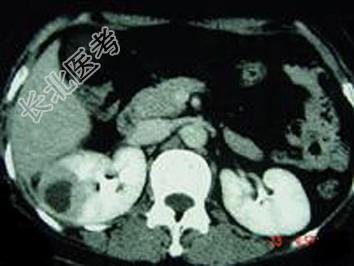

- 单项选择题女,12岁, 右腰部疼痛10天,尿检可见大量的脓细胞 CT平扫+增强如图所示, 应诊断为 ( )

A、右肾脓肿

B、右侧感染性肾囊肿

C、右肾转移瘤

D、右侧肾癌

E、右肾结核